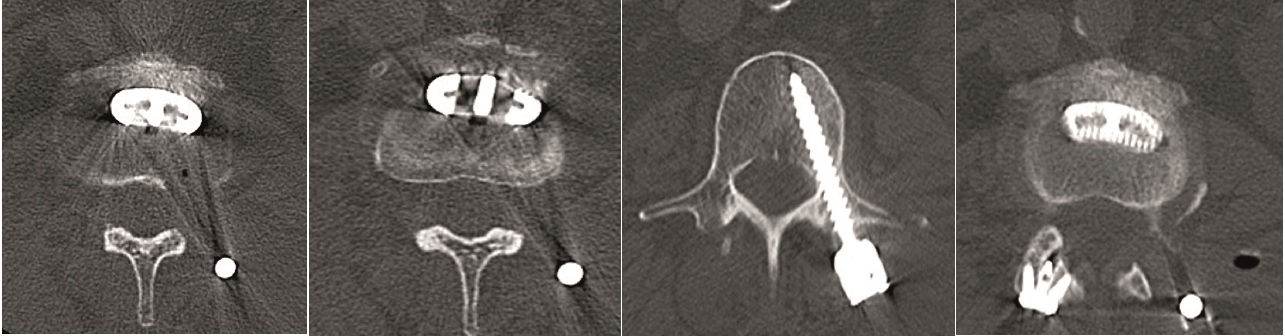

Multilevel facet pathology is shown in Fig 6. Intraoperative and postoperative images are shown (Fig 7-9).

Case 2